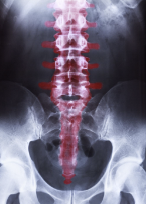

허리 척추협착증에 좋은 운동은 척추 근육을 강화하고 척추를 유연하게 유지하는 것입니다. 척추 근육이 강해지면 척추가 안정되고, 척추의 움직임이 개선되어 허리 척추협착증을 예방하거나 치료할 수 있습니다. 아래는 허리 척추협착증에 좋은 운동입니다.

유산소 운동은 혈액순환을 촉진하고 척추 주변 근육을 강화하는 데 도움이 됩니다. 적절한 운동량과 강도를 유지하면서, 걷기, 수영, 자전거 타기 등의 유산소 운동을 권장합니다.

허리 근육을 강화하고 척추의 안정성을 높이는 근력 운동을 권장합니다. 덤벨을 이용한 데드리프트, 랫 풀 다운, 스쿼트 등의 운동이 있습니다. 하지만, 근력 운동 시 적절한 자세와 기술을 사용해야 합니다.

과한 운동은 오히려 허리를 망칠 수 있으므로 정확한 자세와 고중량이 아닌 저중량으로 살살 하는 것이 좋습니다.

척추를 더 유연하게 만들고 척추 근육의 긴장을 완화시키는 스트레칭을 권장합니다. 허리를 구부리거나 펴는 등의 동작을 하는 스트레칭 운동이 있습니다. 하지만, 스트레칭 시 과도한 끌어당기기는 피해야 합니다.

요가와 필라테스는 척추를 유연하게 만들고 근육을 강화하는 데 도움이 됩니다. 특히, 코브라, 다운워드 동작, 플랭크와 같은 요가 운동과 복부 근육을 강화하는 필라테스 운동이 유용합니다.

수중 운동은 척추 근육을 강화하고 척추에 가해지는 압력을 감소시키는 데 도움이 됩니다. 수영, 아쿠아 에어로빅 등의 운동을 권장합니다.

운동 전에는 적절한 스트레칭과 움직임을 수행하는 것이 중요합니다. 또한, 척추에 이상이 있는 분들은 격하게 하는 것이 아닌 무리가 가지 않는 선에서 하도록 유하셔야 합니다.